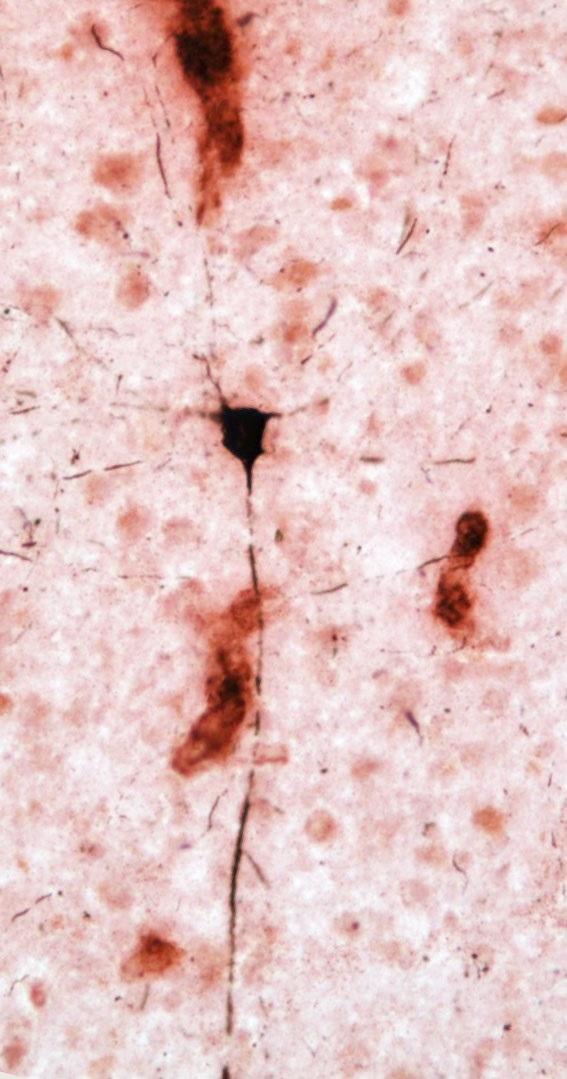

Photo Caption: Kent State University researchers analyzed the brains of aged chimpanzees to show pathology similar to the human Alzheimer's disease brain. This image shows tau-positive neuron (black) in proximity to amyloid deposits within blood vessels (red) in an aged chimpanzee brain.

These findings differ from what we see in humans. While approximately 80 percent of Alzheimer's disease patients also have cerebral amyloid angiopathy, or amyloid beta deposits in the brain's blood vessels that increase the risk for stroke and dementia, the predominant amyloid beta pathology is plaques. Tau lesions also were found in the forms of neurofibrillary tangles and clusters of tau-positive neurites (i.e., pieces of dying neurons).

"Neurofibrillary tangles are observed in Alzheimer's disease patients, but the tau-immunoreactive neuritic clusters in the neocortex appear specific to chimpanzees," said Patrick R. Hof, M.D., Regenstreif professor and vice-chair of neuroscience at Icahn School of Medicine at Mount Sinai. In addition, neurofibrillary tangles pathology was observed in apes that exhibited plaques and moderate or severe cerebral amyloid angiopathy and in one individual with virtually no amyloid beta pathology. "The presence of amyloid and tau pathology in aged chimpanzees indicates these Alzheimer's disease lesions are not specific to the human brain as generally believed," Hof continued.